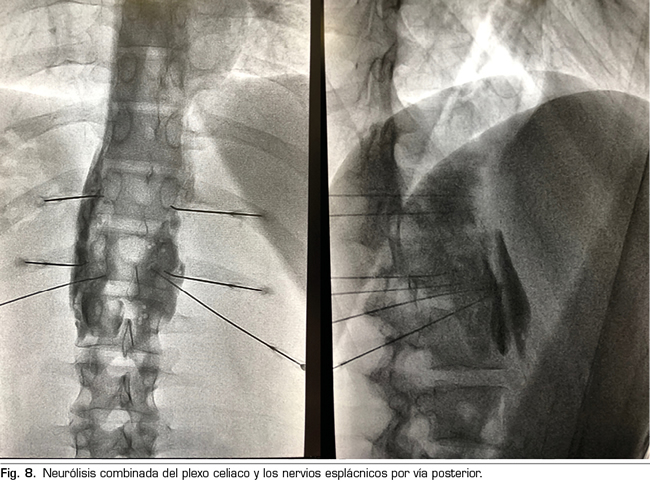

El procedimiento estándar sería el abordaje posterior del plexo celiaco (abordaje clásico), ya que a día de hoy continúa siendo el de mayor evidencia científica, preferiblemente transcrural y guiado por fluoroscopia, debido a su sencillez y rapidez. La ecoendoscopia estaría indicada para la neurólisis aprovechando su indicación diagnóstica o terapéutica, para situaciones de imposibilidad para el decúbito prono, y como alternativa en caso de que falle el abordaje posterior. La neurólisis percutánea ecográfica quedaría reservada para casos seleccionados, dependiendo de la experiencia del operador, ya que es la técnica que menos publicaciones tiene hasta la fecha. Confiamos en que en un futuro se publiquen trabajos que permitan a las técnicas ecoguiadas, ya sean percutáneas o ecoendoscópicas, ocupar el puesto de “método de referencia”, ya que permiten la visualización de las estructuras circundantes con control de la inyección en tiempo real. Una alternativa al bloqueo del plexo celiaco es la radiofrecuencia convencional de los nervios esplácnicos, indicada cuando existe infiltración tumoral del tronco celiaco, alteraciones anatómicas importantes o si fracasa la neurólisis del plexo celiaco. También es posible considerar una neurólisis combinada —bloqueo neurolítico del plexo celiaco asociado a bloqueo neurolítico o radiofrecuencia de los nervios esplácnicos—, como refleja el trabajo de Marra y cols. (60), y como venimos realizando en nuestra práctica clínica habitual en HM hospitales, con el objetivo de aumentar la tasa de éxito y la duración de la analgesia sin aumentar la incidencia de complicaciones, pero hasta ahora no hay trabajos comparativos suficientes para apoyar esta hipótesis (Figura 8).